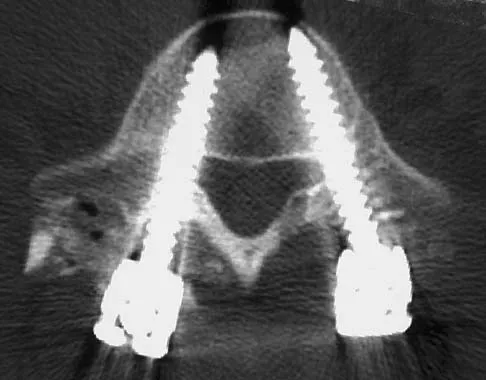

Question 79

Figures 40a and 40b show the pre- and postoperative radiographs of an 82-year-old woman with bilateral hip pain who has had staged total hip arthroplasties. To minimize potential injury to the sciatic nerve at the time of surgery, the surgeon should

Explanation